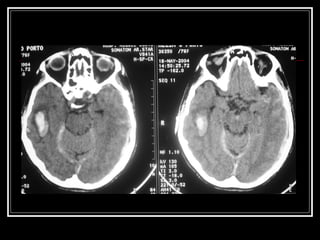

Diagnóstico TC de crânio sem contraste na fase aguda do evento  Limitações: Infratentorial tronco Outros: Lobar? Idade < 45 anos?Hemoventrículo solitário?Sem HAS? RNM e suas variações, arteriografia, etc. para investigação da etiologia do sangramento HDA e HPP (trauma? Anticoagulação? Drogas? Dça hematológica)

Diagnóstico TC decrânio sem contraste na fase aguda do evento Limitações: Infratentorial tronco Outros: Lobar? Idade < 45 anos?Hemoventrículo solitário?Sem HAS? RNM e suas variações, arteriografia, etc. para investigação da etiologia do sangramento HDA e HPP (trauma? Anticoagulação? Drogas? Dça hematológica)